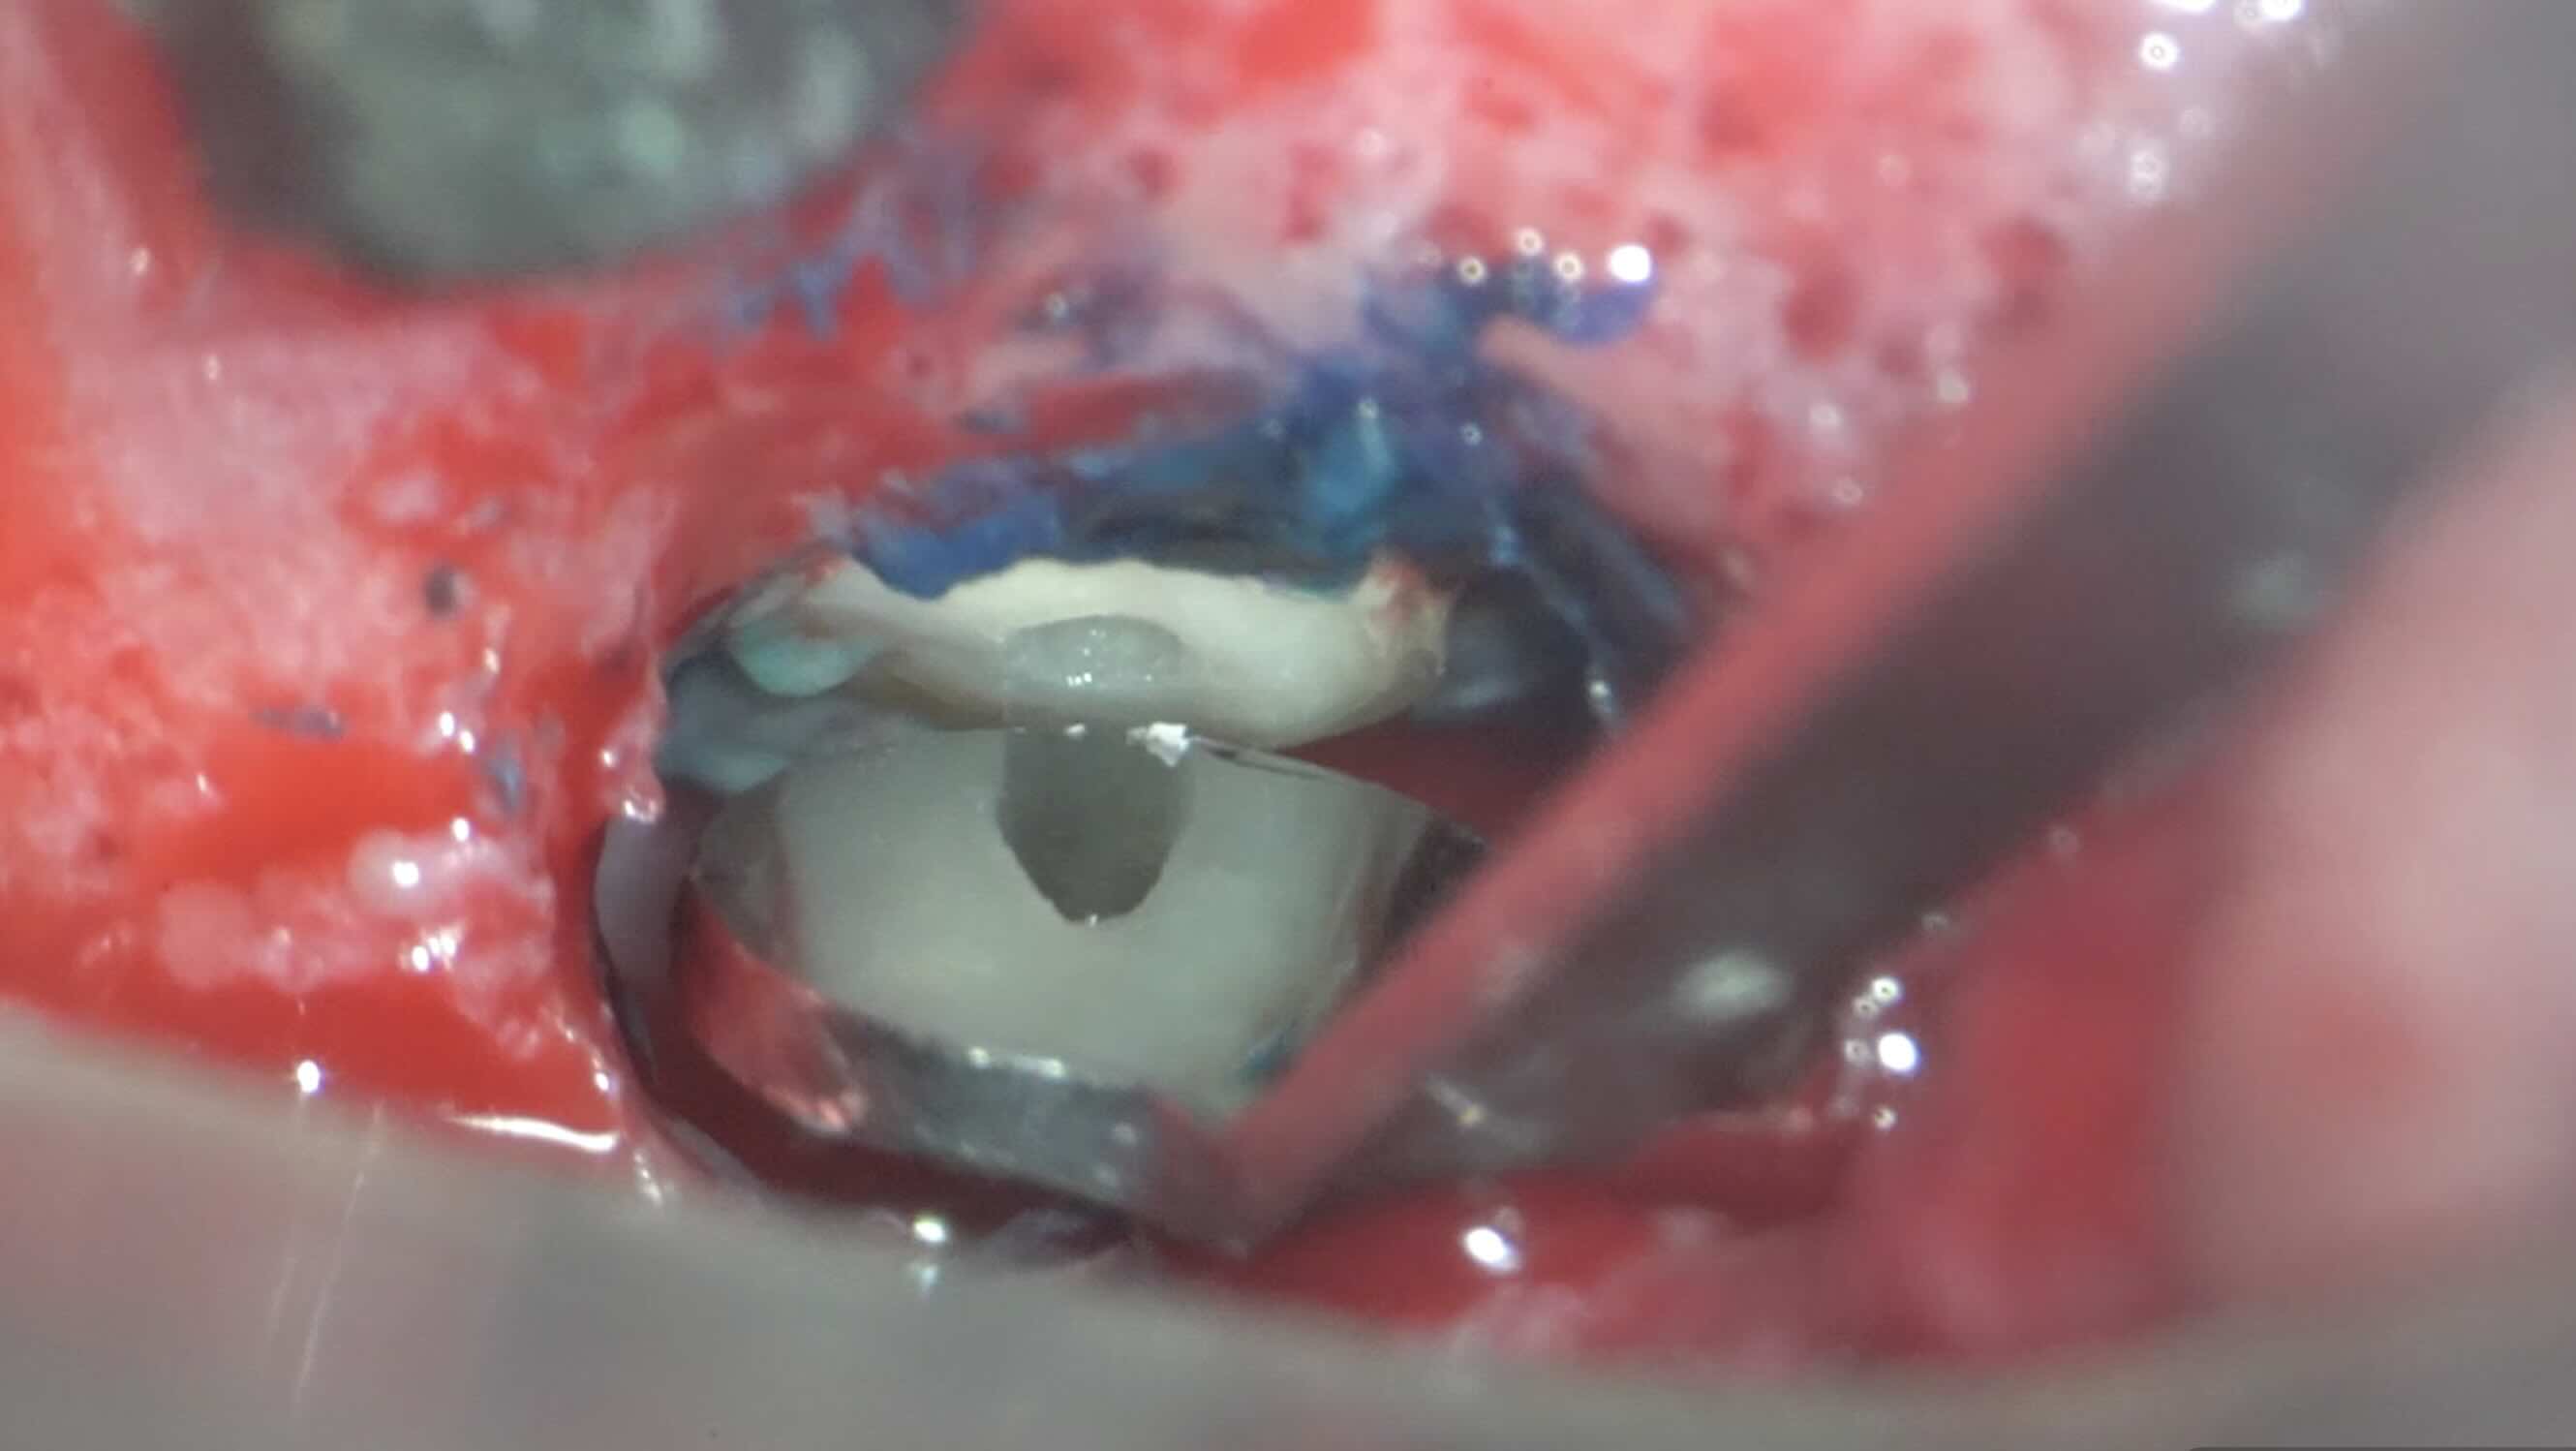

歯根の先端を出して、確認します

歯根の先端を約3mm切断後、根管を確認します。

根の先を切るだけでは治りません。

根管内部の感染を取り除く処置(逆根管形成)がとても重要になります。

これにより、根管内部の細菌数を減らしています。

外科治療と言っても、やっていること(目的)は、通常の根管治療と同じです。

その後、しっかりと封鎖します。